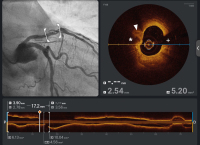

Abbildung 3: OCT revealed a fibro-calcified plaque with lipid deposits (* = calcified areas, arrowhead = lipidic/fibrotic plaque, + = guidewire artefact)

Abbildung 4A-B: Buddy ballon technique: 2 wires (Turntrac™) advanced into the LAD. 1.5 (1 dot in the centre) and 2.5 mm (two dots at the edges) NC-balloons placed in parallel in the heavy calcified proximal LAD and inflated simultaneously with high pressure (A). Stent deployment (DES; 4.0 x 28 mm) (B)

Abbildung 5: OCT images post ballon angioplasty using buddy ballon technique. Several cracks and fractures were displayed by OCT imaging (* = fibro-calcified plaque, arrowhead = rupture, + = guidewire artefact)

Abbildung 6: OCT post stent implantation showed good stent apposition and expansion and satisfying minimal stent area (arrowheads = stent struts, + = guidewire artefact)